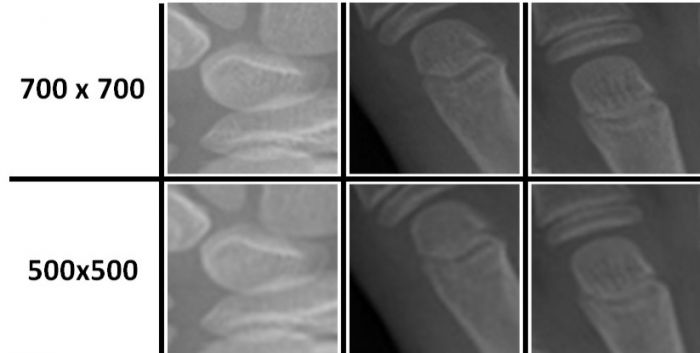

Bone Age Assessment (BAA) is a task performed by physicians to estimate the skeletal development of a pediatric patient. Tipically physicians perform this exam by doing a manual analysis of the X-ray image of the non-dominant hand of a child, either by taking the image as a whole or paying attention to certain anatomical Regions Of Interest (ROIs). Over the years, several datasets have been proposed in order to generate automated methods to perform this task. Most notably, in 2017 the Radiological Society of North America (RSNA)1 created the Pediatric Bone Age Challenge, which encouraged the development of machine learning approaches for this task. In this paper, we present GPNet a convolutional neural network capable of performing BAA precisely and effectively by analyzing the whole hand in a single forward pass. We train GPNet using the training data available from the dataset created in the RSNA challenge and evaluate our method using the validation set. We use the testing set to compare our performance with the current state-of-the-art and find that GPNet significantly outperforms previous methods. During our architecture search we perform several experiments to demonstrate the effect of different layers, proving that some blocks do not contribute to the performance of the network, but instead they affect it. As a result, we are able to develop a method that reduces the number of trainable parameters by nearly 82.15 M in comparison to the state-of-the-art, while improving the performance.